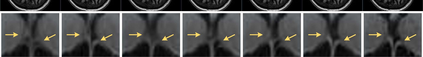

The thick-slice magnetic resonance (MR) images are often structurally blurred in coronal and sagittal views, which causes harm to diagnosis and image post-processing. Deep learning (DL) has shown great potential to re-construct the high-resolution (HR) thin-slice MR images from those low-resolution (LR) cases, which we refer to as the slice interpolation task in this work. However, since it is generally difficult to sample abundant paired LR-HR MR images, the classical fully supervised DL-based models cannot be effectively trained to get robust performance. To this end, we propose a novel Two-stage Self-supervised Cycle-consistency Network (TSCNet) for MR slice interpolation, in which a two-stage self-supervised learning (SSL) strategy is developed for unsupervised DL network training. The paired LR-HR images are synthesized along the sagittal and coronal directions of input LR images for network pretraining in the first-stage SSL, and then a cyclic in-terpolation procedure based on triplet axial slices is designed in the second-stage SSL for further refinement. More training samples with rich contexts along all directions are exploited as guidance to guarantee the improved in-terpolation performance. Moreover, a new cycle-consistency constraint is proposed to supervise this cyclic procedure, which encourages the network to reconstruct more realistic HR images. The experimental results on a real MRI dataset indicate that TSCNet achieves superior performance over the conventional and other SSL-based algorithms, and obtains competitive quali-tative and quantitative results compared with the fully supervised algorithm.